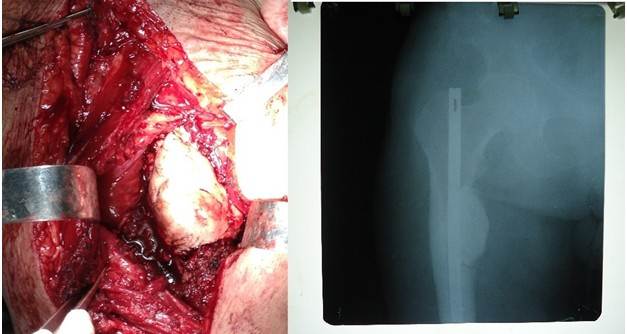

El cemento quirúrgico es muy empleado para el llenado de las cavidades destruidas por el tumor, tiene actividad antineoplásica no solo por el efecto de la polimerización, sino también por los tóxicos directos de los monómeros a las células tumorales; y por el alto calor que produce. Sin embargo existen complicaciones relacionadas con su uso como: muerte súbita por arritmias cardiacas, tromboembolismo pulmonar, infecciones tardías y fractura de los extremos de la cementación (Figura 4). 44,45,46

En los tumores óseos metastásicos de las extremidades con gran tamaño y muy vascularizados resulta útil el control vascular proximal, que disminuye de manera significativa el sangrado durante la cirugía y así facilita una resección más efectiva (Figura 5).